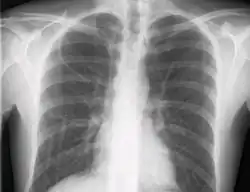

Le contrôle radiologique de la position de la voie doit être fait par une radiographie du thorax.

Radio du thorax avec la veine sous-clavière droite cathétérisée

Le cathétérisme de la veine sous-clavière s'effectue dans des conditions d'asepsie chirurgicales. Pour un opérateur droitier, la veine sous-clavière gauche est la plus accessible. L'aiguille est introduite sous la clavicule, à la distance de deux travers de doigt du sternum en direction de l'épaule opposée. La main droite de l'opérateur introduit l'aiguille pendant que la gauche détermine les reliefs osseux par palpation. De la même manière, un guide est introduit par l'aiguille dès que la veine est cathétérisée. Le guide sert de tuteur à l'introduction de la voie. Cette dernière est fixée à la peau par suture. Un contrôle radiologique de la position de la voie est effectuée afin de ne pas laisser l'extrémité de la voie toucher les cavités cardiaques. On vérifie par le même examen l'absence de pneumothorax.